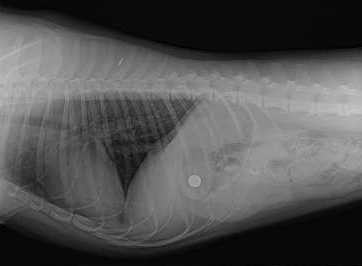

They did the surgery around 1-2 a.m. on Wednesday.  When they first opened her up, they couldn't find the battery, even though it clearly showed on the x-rays. So they closed her up and took another x-ray, and, sure enough, it was still there!  The problem was, it was at the juncture between the stomach and intestines, so it was a bit difficult to find by feel.  I was really worried, because if they couldn't get it, that would mean they'd need to just try to let it pass naturally, which would be not so good an idea if the battery were punctured (and it was hard to tell whether or not it was, from the x-ray).  So...I was kind of anxious and didn't really sleep at all that night, waiting to find out.  They went in again, and, when I called them at 5 a.m., they said they had been finally been able to find it and remove it.  I was so relieved!  Luckily, it wasn't punctured, and only had been blackened on the outside by her gastric juices.  Here’s a lovely photo, of where it was (they now give you copies of their x-rays on a CD!), and of the infamous culprit (originally, remember, the battery was silver!):